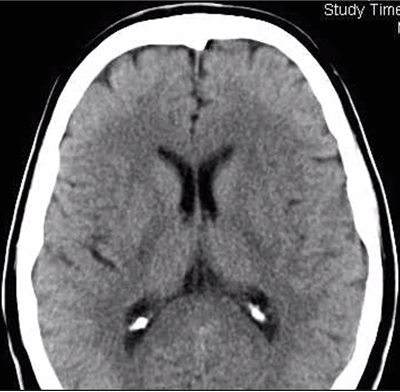

Vad ses på denna DT?